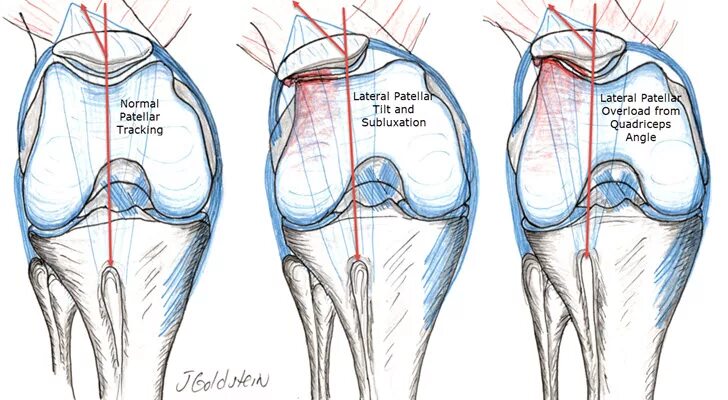

Вывих надколенника код мкб 10